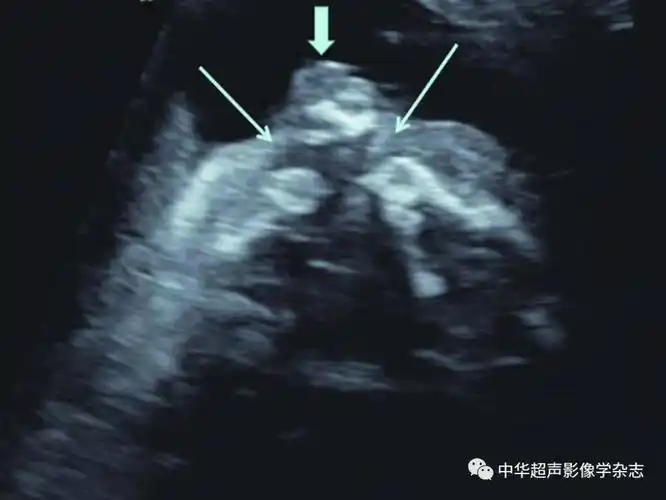

(箭头所示);b:正常胎儿面部正中矢状面下唇裂非常罕见且超声诊断困难